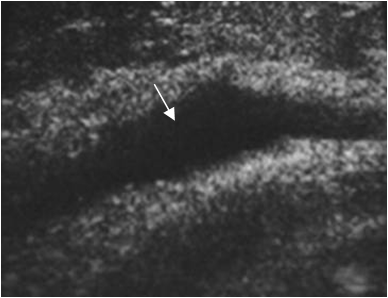

Fig 53 B. Derrame articular.

Ecografía. Presencia de moderada cantidad de líquido articular, por artritis séptica de rodilla.

La ecografía es muy sensible para detectar derrame articular. Adicionalmente sirve para guiar la artrocentesis. (11, 20). (Fig 53 B).